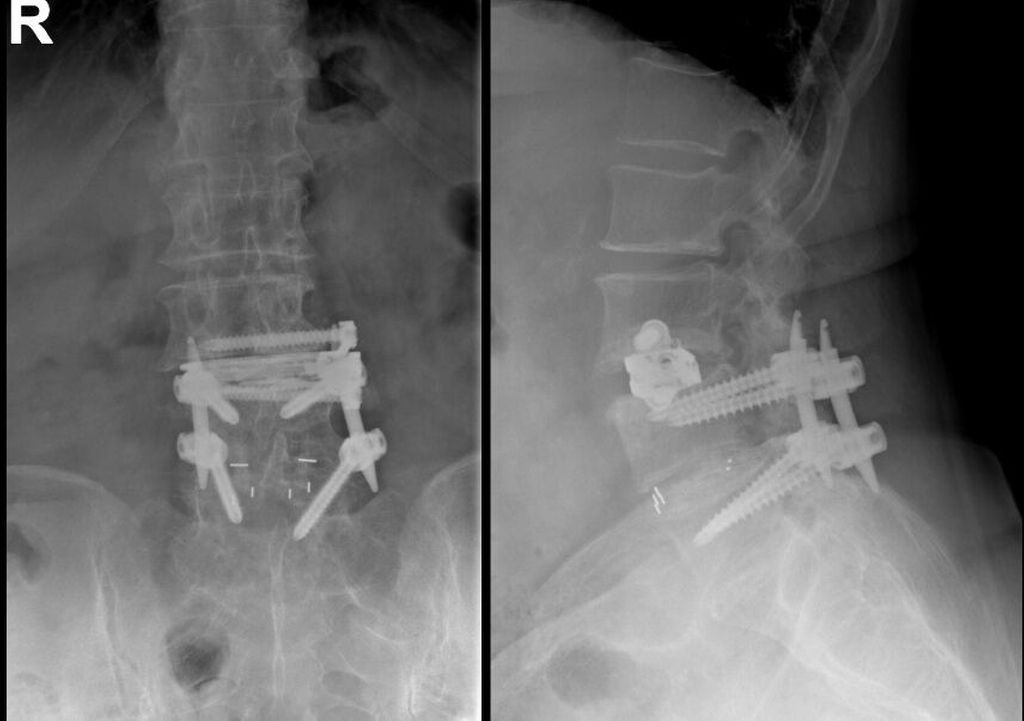

Fallbeispiel 2

TLIF über Mittellinienzugang mit Schrauben in „cortical bone trajectory“. Bei der 63-jährigen Patientin bestand eine degenerative Spondylolisthese Meyerding Grad I mit Facettengelenkszysten und Wirbelkanalstenose (Abb. 8). Klinisch bestanden Lumboischialgien mit Ausstrahlung dem Dermatom L5 bds. entsprechend. Es wurde ein Mittellinienzugang durchgeführt und zuerst wurden navigierte Schrauben in „cortical bone trajectory“ platziert (Abb. 9). Anschließend erfolgten eine Facettektomie L4/5 links und eine Dekompression des Wirbelkanals. Abbildung 10 zeigt, dass der Hautschnitt aufgrund der mittelliniennahen Schraubenköpfe klein gehalten werden kann. Klinisch wurden die lumbalen Schmerzen wie ausstrahlende Beschwerden 1 Jahr postoperativ annähernd vollständig behoben, die korrespondierende Röntgenkontrolle ist in Abbildung 11 dargestellt.